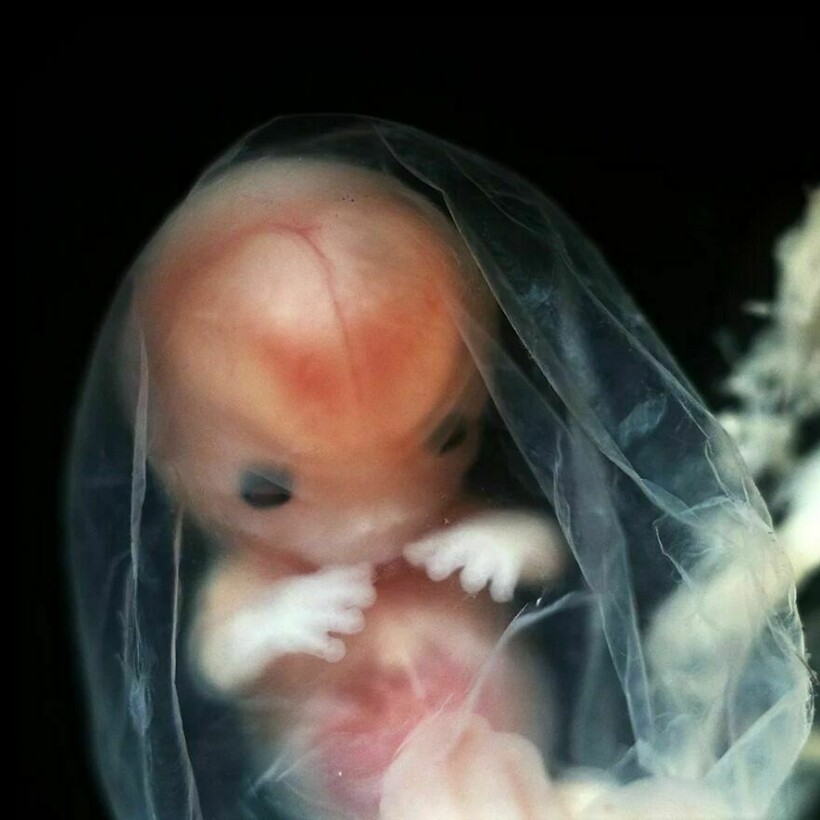

Леннарт Нильссон стал настоящей легендой фотографии, ведь он сделал то, чего не удавалось никому: показал миру, как развивается ребенок в утробе матери. Его проект «Ребенок родился» был создан в 1960-х годах, и он представляет собой детальные снимки эмбрионов на разных стадиях развития. Фотографии стали сенсационными, впервые они появились в журнале LIFE, и одна из них украсила обложку. На протяжении многих лет эти снимки публиковали в разных журналах.

Фотограф снимал детей в утробе матерей во время медицинских процедур

Он присутствовал на амниоцентезе и лапароскопии

Нильссон не скрывал, что снимал и эмбрионы после выкидышей и абортов

Снимки стали сенсацией, их много раз перепечатывали, они и сегодня вызывают отклик у зрителей

Его фото позволили заглянуть в чудо рождения, они стали источником знаний и вдохновения